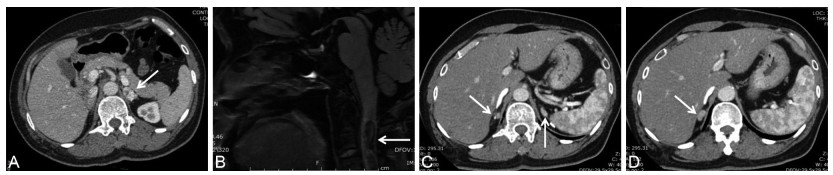

• This paper reported a patient presented with recurrent bilateral adrenal pheochromocytoma combined with cervical medullary hemangioblastoma, renal cyst, and pancreatic cyst, she had a first-degree relative with renal clear cell carcinoma and was diagnosed as Von Hippel-Lindau (VHL) disease. Genetic testing further confirmed the diagnosis. We summarized the clinical characteristics of VHL disease with adrenal pheochromocytoma reported in the literatures in the past 10 years. Patients with bilateral, recurrent or metastatic pheochromocytoma, or with central angioblastoma, retinal hemangioblastoma, renal cancer, pancreatic neuroendocrine tumor, cyst and cystadenoma of the reproductive system should be highly suspected of VHL disease. We should carry out genetic testing and family investigation as to avoid missed diagnosis and misdiagnosis.